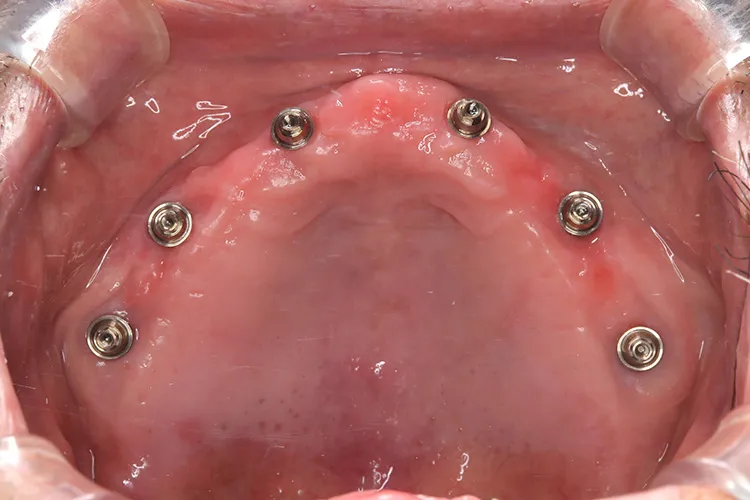

症例7/

上顎ボーンアンカードブリッジ

- 治療期間

- 6ヶ月

- 費用

- 285万円(税込)

治療前

治療後

レントゲン画像

治療内容

上顎の総入れ歯が不安定で固定式を希望され、インプラント6本で上部構造を支えるボーンアンカードブリッジを選択されました。インプラント埋入したその日にそれまで使用していた入れ歯をインプラントに固定させました。その後歯肉が治癒した段階で最終の上部構造(14本ブリッジ)を装着しました。